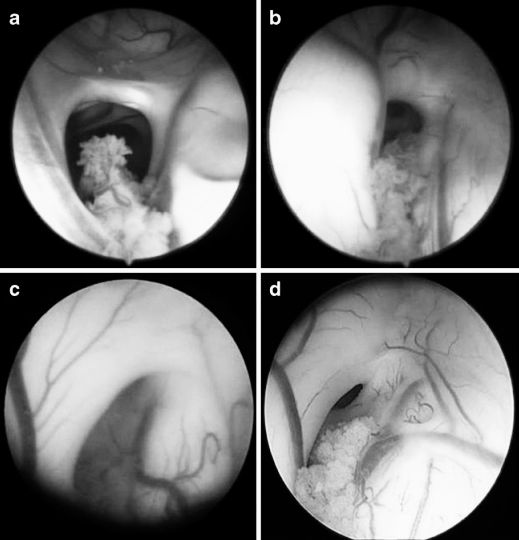

图3 内镜下右侧室间孔的不同形态,提示第三脑室穿刺难度逐渐增大。a 水平型 b 斜向型 c 垂直型 d 垂直且孔径缩小型